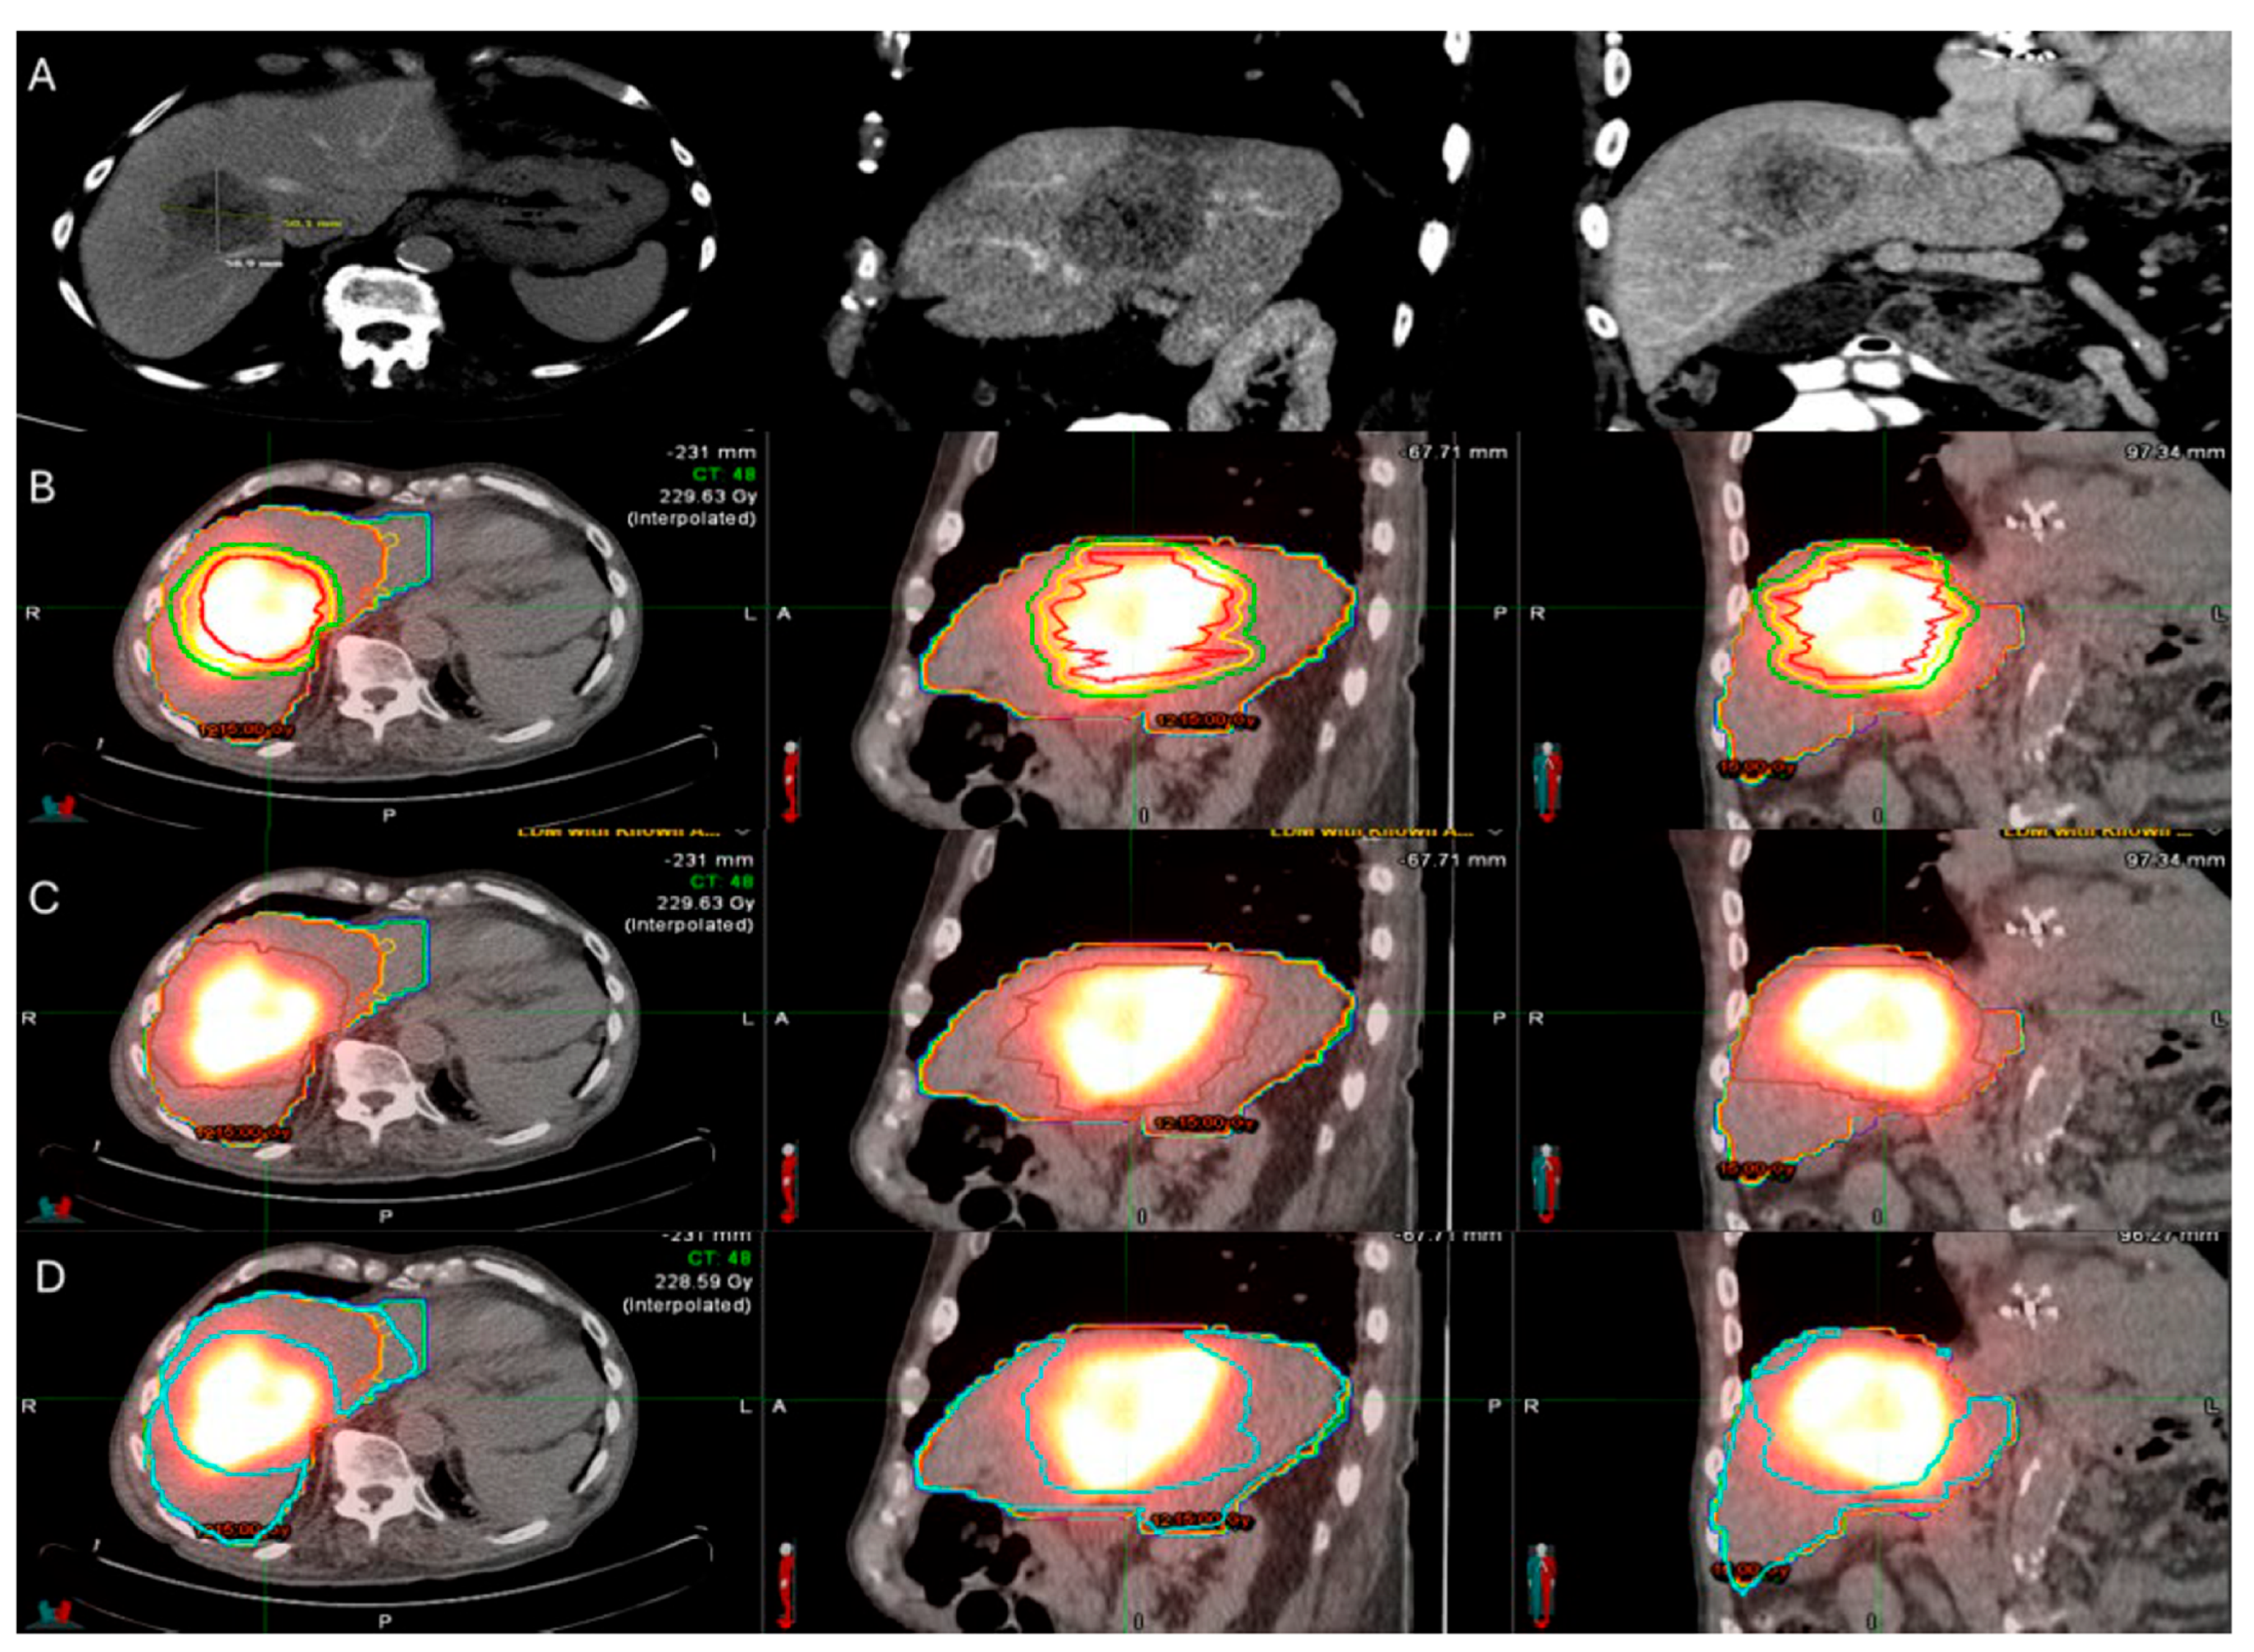

Another major limitation of TA was the lack of a reliable confirmation method of adequate uniform coverage of the target tumor by the AZ with the desired MM as depicted on cross sectional imaging [70]. In the early 2000s, there was no standardization of the MM evaluation. Ideal timing and assessment methodologies after completion of the ablation procedure were lacking. Initial assessments were based on 2-dimensional (2D) side-by-side comparisons of the pre- and the post-ablation ceCT [9,79,83,84,85,86,87]. A pivotal study evaluating the importance of the MM performed a two-dimensional assessment of the AZ and confirmed the MM constitutes an independent predictive factor of LTP after RFA. The reported reduction in LTP rate risk was 46% for each 5 mm increase in minimal margin size [70]. The authors proposed the immediate assessment of the MM intra-operatively for ablation completeness in addition to the efficacy assessment with a 4 to 8 weeks post-ablation imaging and the standardization of a reliable assessment methodology for margin verification [70]. Following studies demonstrated a statistically significant inverse relationship between LTP and MM ≥ 5 mm and no instances of LTP for tumors treated with MM ≥ 10 mm [79,88]. In KRAS mutant CLM, MM ≥ 10 mm are recommended to optimize oncologic outcomes [41,85,86,89,90]. Even for tumors with aggressive biological characteristics, achieving complete tumor ablation, characterized by sufficient margins and verified negative biopsy results from the ablation zone, remains the most significant predictor for effective local control. This comprehensive eradication significantly reduces the risk of local tumor recurrence and is considered the most vital factor in successful treatment control outcomes [91]. The literature supported that intraprocedural MM assessments have greater predictive value on LTP rates in comparison to the historic standard of 4–8 week post-ablation assessements [92,93]. Subsequent investigations indicated that volumetric 3D MM assessments are more reliable and consequently more accurate for predicting risk and location of LTP than the 2D side-by-side comparisons [13]. Specialized software systems allow pre- and post-ablation image registration and 3D evaluation of the AZ and margins (Figure 1) [70,92,93,94,95,96,97,98,99,100]. The use of biomechanical model-based deformable image registration (DIR) software (Morfeus, RayStation, RaySearch Laboratories, Stockholm, Sweden) combined with artificial intelligence autosegmentation has recently been validated as an essential method for confirming ablation completeness in hepatic tumors. A randomized phase II trial demonstrated that this approach accurately quantifies the minimal ablative margin and effectively predicts local tumor control after ablation of primary and secondary liver tumors (COVER-ALL) [101]. A statistically significant superiority in achieving MM ≥ 5 mm when they used this validation method in comparison to visual-only side-by-side AZ assessment was documented [101].

Figure 1.

56-year-old male with history of colorectal cancer under chemotherapy treatment presents with new segment 5 liver metastasis on T1 Magnetic Resonance Imaging with fat suppression (A) and fluorodeoxyglucose Positron Emission Tomography and Computer Tomography (FDG-PET/CT) (B) and undergoes microwave ablation (MWA). The target tumor is visible on the contrast enhanced Computer Tomography (ceCT) on ablation day imaging (C). Administration of the first FDG dose according to the split-dose PET/CT protocol (4 mCi), the FDG-avid tumor is clearly visualized (D). Hydrodissection is utilized to protect the adjacent ascending colon. After administration of the second FDG dose (8 mCi), the photopenic ablation zone indicates absence of residual metabolic activity (E). Ablation technical success is confirmed on post-ablation ceCT with utilization of MIM DEV software version 3.3.7. Red circle represents the tumor contours, yellow circle and green circle represent the 5 and 10 mm (mm) margins around the target tumor, respectively. The blue circle represents the contours of the ablation zone that uniformly covers the tumor with 5 mm margins, confirming technical success of thermal ablation (F). Follow-up anatomic and metabolic imaging at 2 years demonstrates involution of the ablation zone (G) with sustained local disease control (H).

The ongoing international, multicenter, single-arm phase II/III clinical trial ACCLAIM (Ablation with Confirmation of Colorectal Liver Metastasis) is designed to demonstrate that intraprocedural confirmation of a 3D MM of at least 5 mm, or immediate re-ablation when the margin is less than 5 mm, can achieve local tumor control rates exceeding 90%. This trial employs advanced margin confirmation software during MWA of CLM to objectively verify sufficient ablation margins in real time. By mandating a minimal 5 mm margin as the criterion for procedural success and allowing immediate corrective intervention, ACCLAIM aims to establish reproducible technical standards for ablation and improve long-term oncologic outcomes.